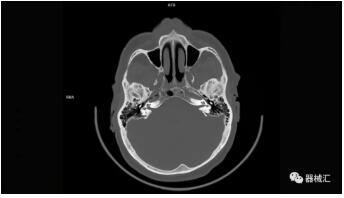

▲ SOMATOM On.site圖像